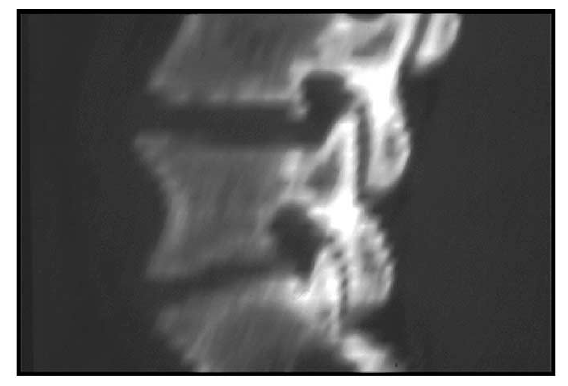

(i) midline sagittal T1-weighted MRI showing degeneration of the L3-L4 and L4-L5 intervertebral disks and associated flattening in the superoinferior dimension, and elongation in the anteroposterior dimension of the intervening L4 vertebral body (middle double-headed arrow); note the relative normal dimensions of the L1 and L5 vertebrae (upper and lower double-headed arrows, respectively) by comparison (compare with (A)).

(ii) Parasagittal T1-weighted MRI showing anteroposterior narrowing of the L4-L5 spinal neural foramen (arrow) as a consequence of the vertebral body elongation at the L4 level (compare with (B)); some superoinferior narrowing of the L4-L5 neural foramen is also present as a result of L4-L5 degenerative intervertebral disk collapse (asterisk).